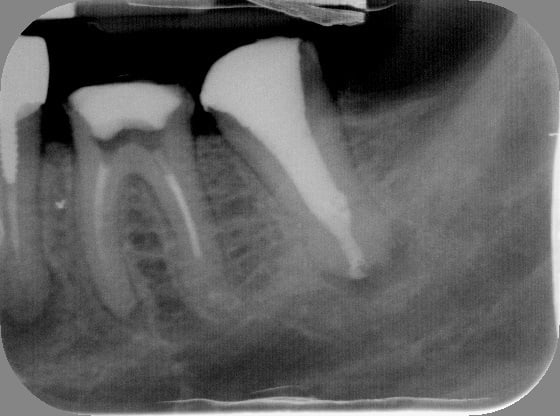

la dent du président

15/11/2011 à 01h11

Content de moi.

Gutt-A

15/11/2011 à 01h23

Tu m'etonnes...avec une racine pareille on se donne tous les moyens pour ne pas avoir a l'extraire un jour...:))

Jolie endo.

En fait, c'est la même endo, le radios ont été interverties la finale a été prise sans clamp.... mais l'endo à été faite sous digue.